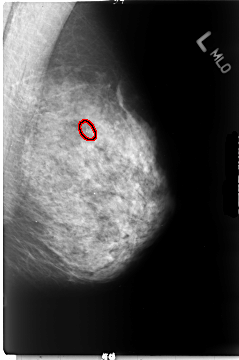

B_3044_1.LEFT_MLO

LEFT_MLO LINES 4680 PIXELS_PER_LINE 3096 BITS_PER_PIXEL 12 RESOLUTION 50 OVERLAY

FILE: B_3044_1.LEFT_MLO.OVERLAY

TOTAL_ABNORMALITIES 1

ABNORMALITY 1

LESION_TYPE CALCIFICATION TYPE PLEOMORPHIC DISTRIBUTION CLUSTERED

ASSESSMENT 4

SUBTLETY 4

PATHOLOGY MALIGNANT

TOTAL_OUTLINES 1

BOUNDARY